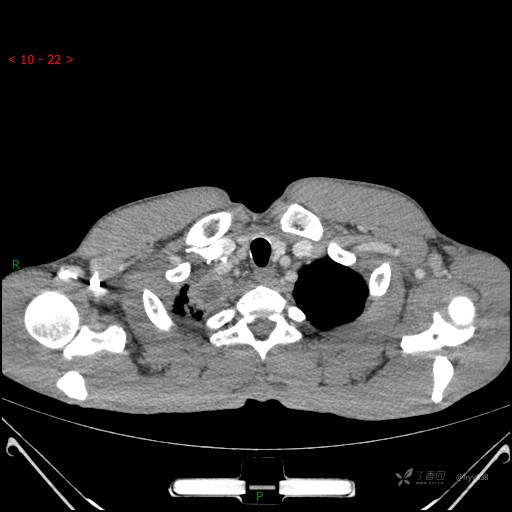

静脉期